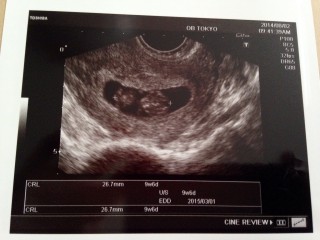

流産経験あり。重度の男性不妊(数少ない、奇形率が高い、運動率0~10%前半)で自然妊娠は難しいと言われ、顕微授精を受ける寸前での自然妊娠です。先生にもここまで育たないと思われていました。今のところ順調ですごく嬉しいです(*^^*) がんばれ我が家の初赤ちゃん!

予定日は、3/1

CRL2.3cm(^^)2週間前は白い丸に心臓がピコピコしていただけなのに、今回は頭、手、足、体がはっきり見えました。ちーっちゃい手をパタパタ動かしてて思わず『可愛い~』と言ってしまいました(^^;先生にも順調と言われ一安心です☆